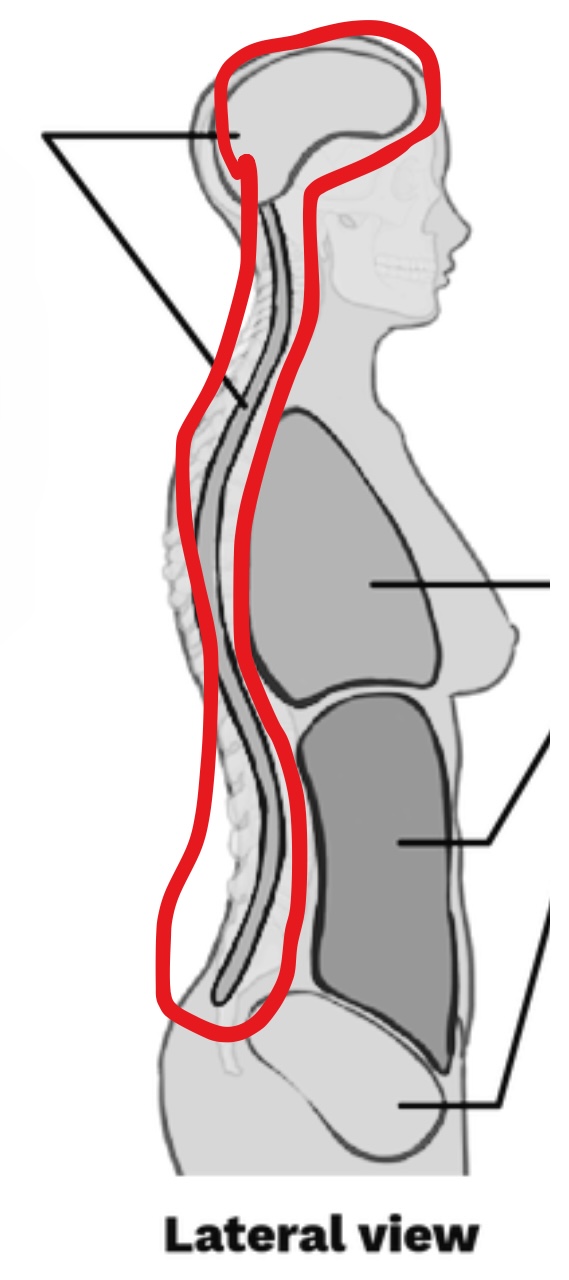

What cavity is this?

Dorsal Cavity